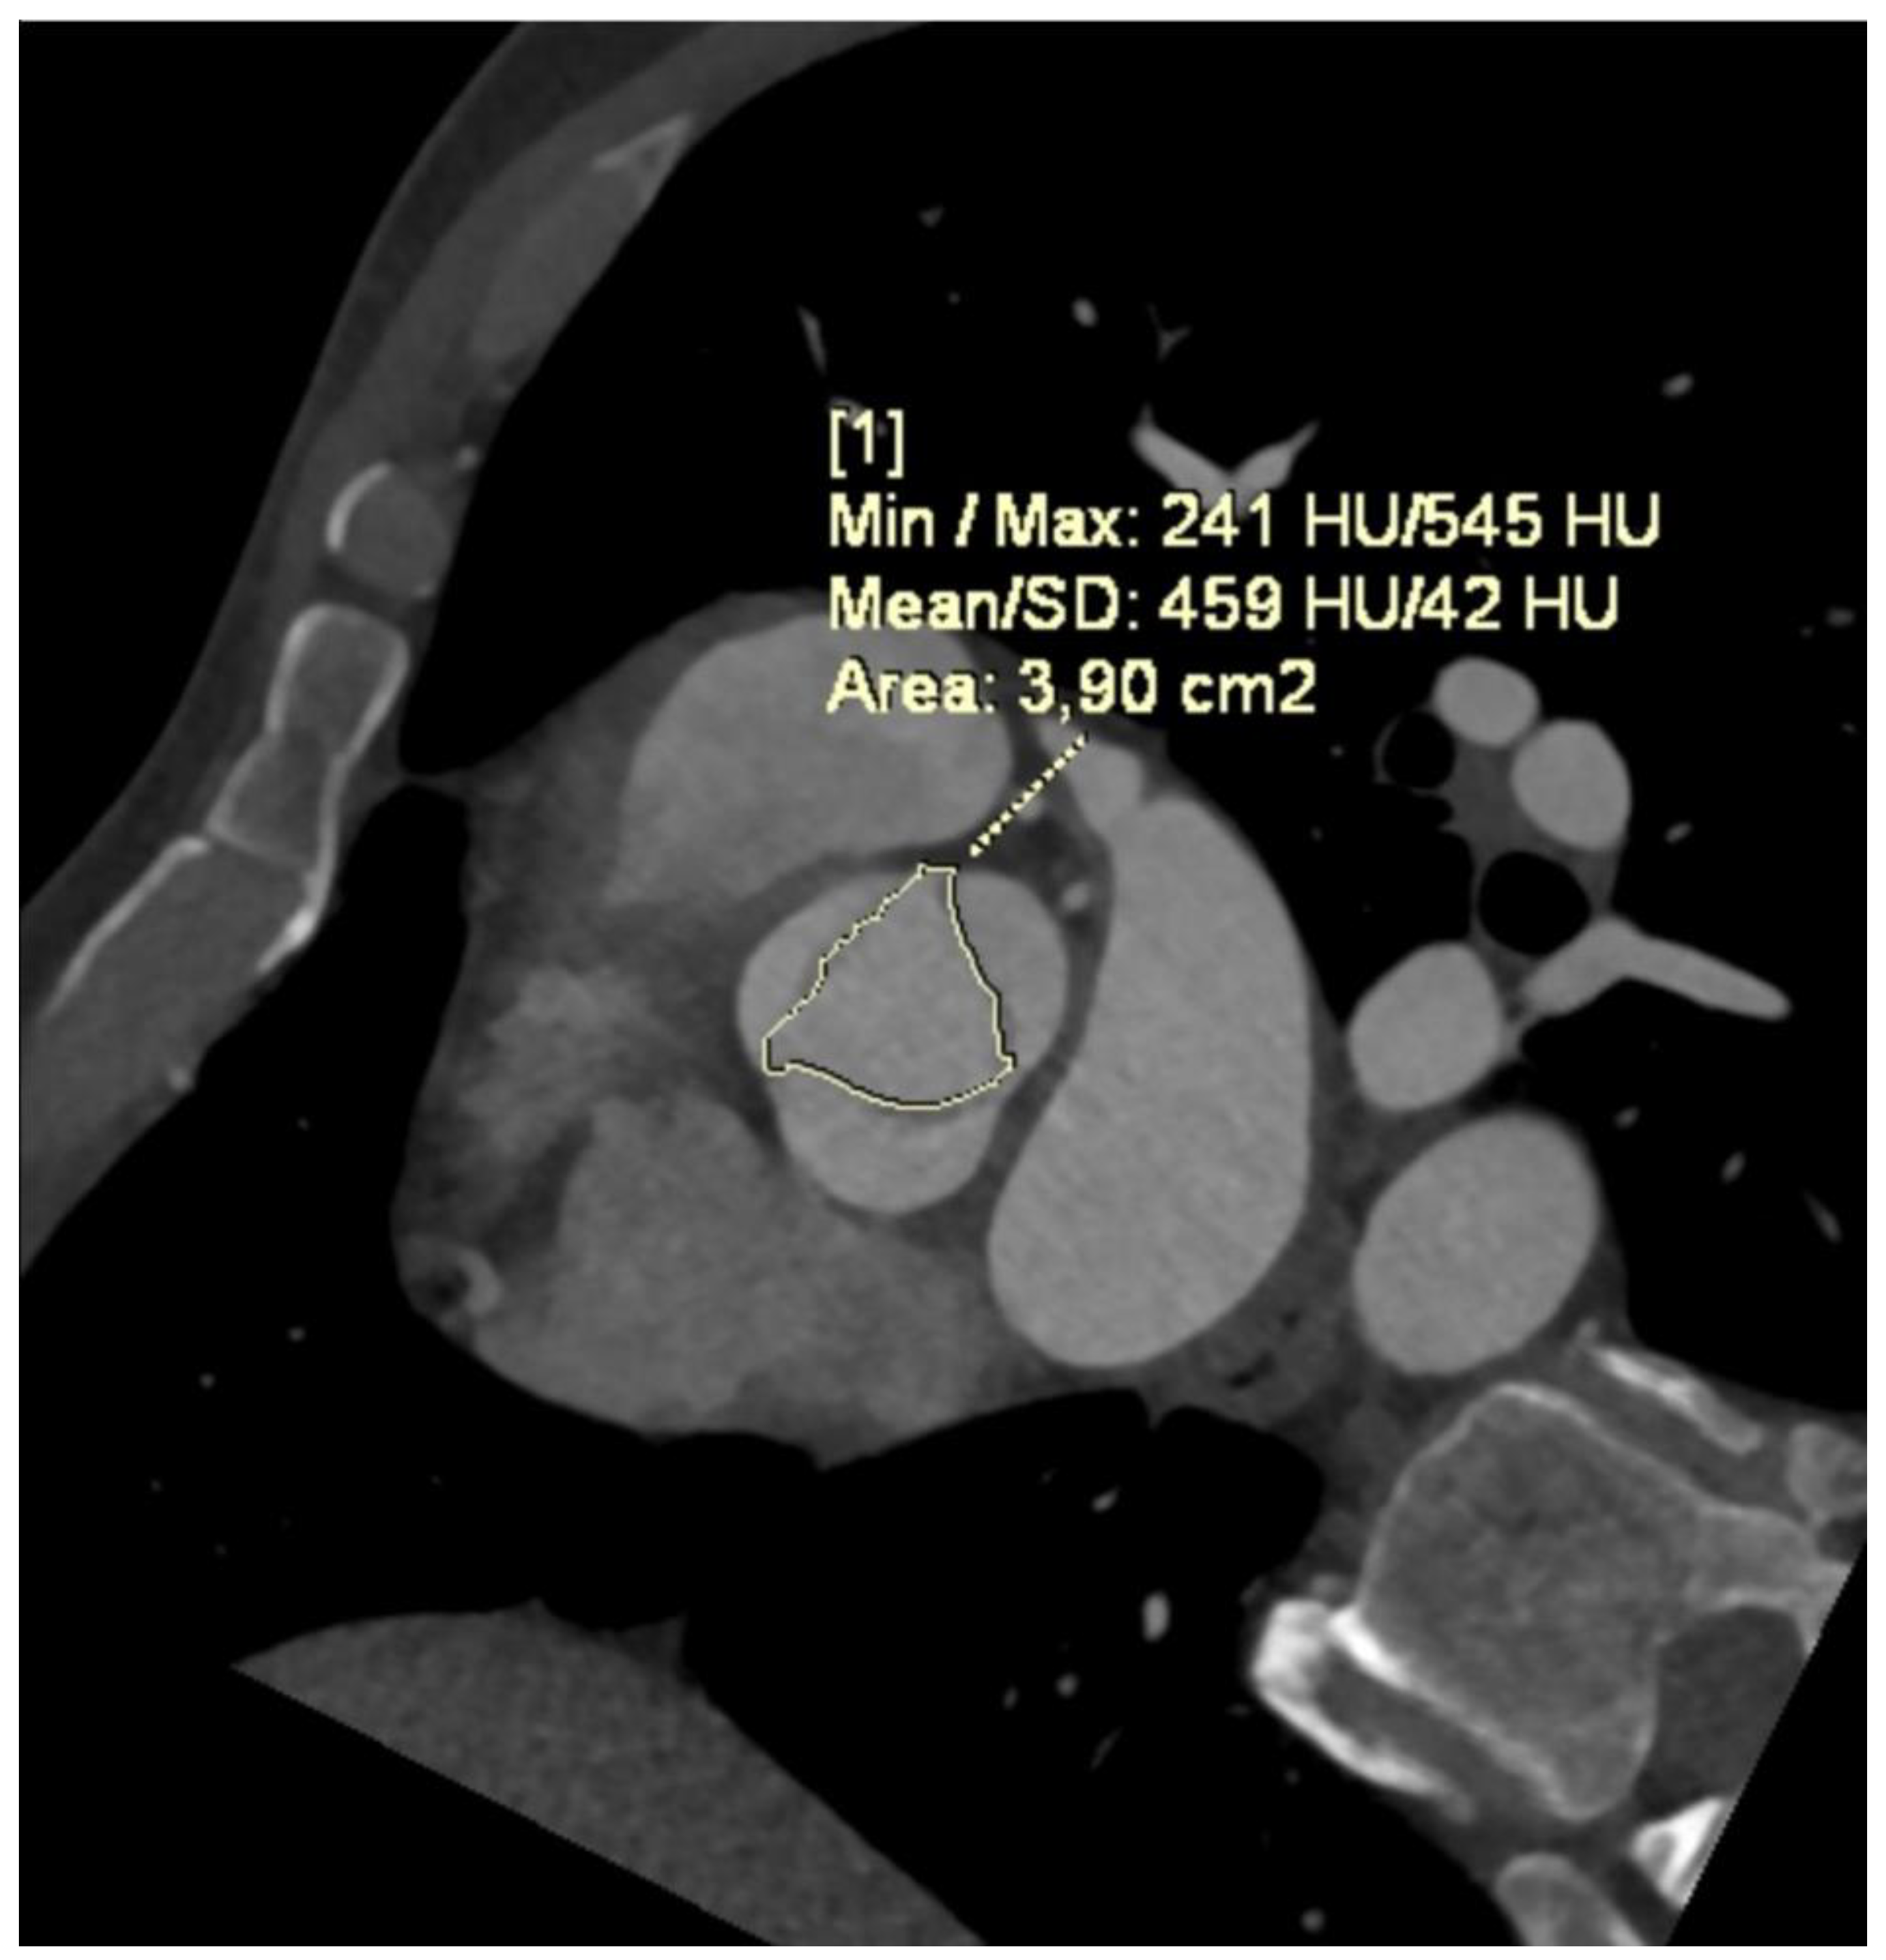

- Angelillis, M.; Costa, G.; De Backer, O.; Mochi, V.; Christou, A.; Giannini, C.; Spontoni, P.; De Carlo, M.; Sondergaard, L.; Miccoli, M.; et al. Threshold for calcium volume evaluation in patients with aortic valve stenosis: Correlation with Agatston score. J. Cardiovasc. Med. 2021, 22, 496–502. [Google Scholar] [CrossRef] [PubMed]